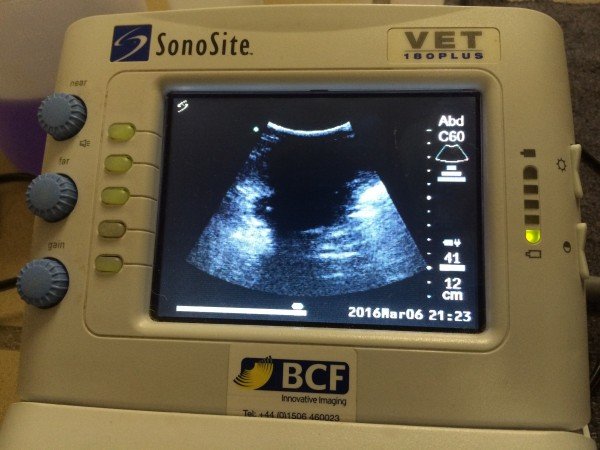

Lady’s Ultrasound – New Puppies on the Way

Today the vet team (Andrew DiSalvo, Emma Alfonso, and Liz Wood) performed an abdominal ultrasound on Lady, one of our Anatolian Shepherd dogs. We use ultrasound as a tool to detect pregnancy, and today’s results show that she is pregnant with her first litter! The gestation period (pregnancy length) in a dog is 63 days. Abdominal ultrasound can be used to detect pregnancy in a female dog as early as 20-25 days of gestation. Ultrasound provides a non-invasive way to check for pregnancy; gel is applied to the animal’s fur and skin to ensure good contact with the ultrasound probe, and an image of the structures beneath the skin appear on a screen as the probe is moved by the veterinarian. While Lady is in the early stages of her pregnancy, an embryo was visible today (the white dot on the ultrasound machine picture). We will recheck her again in a few weeks to see if her pregnancy is still on a healthy path.